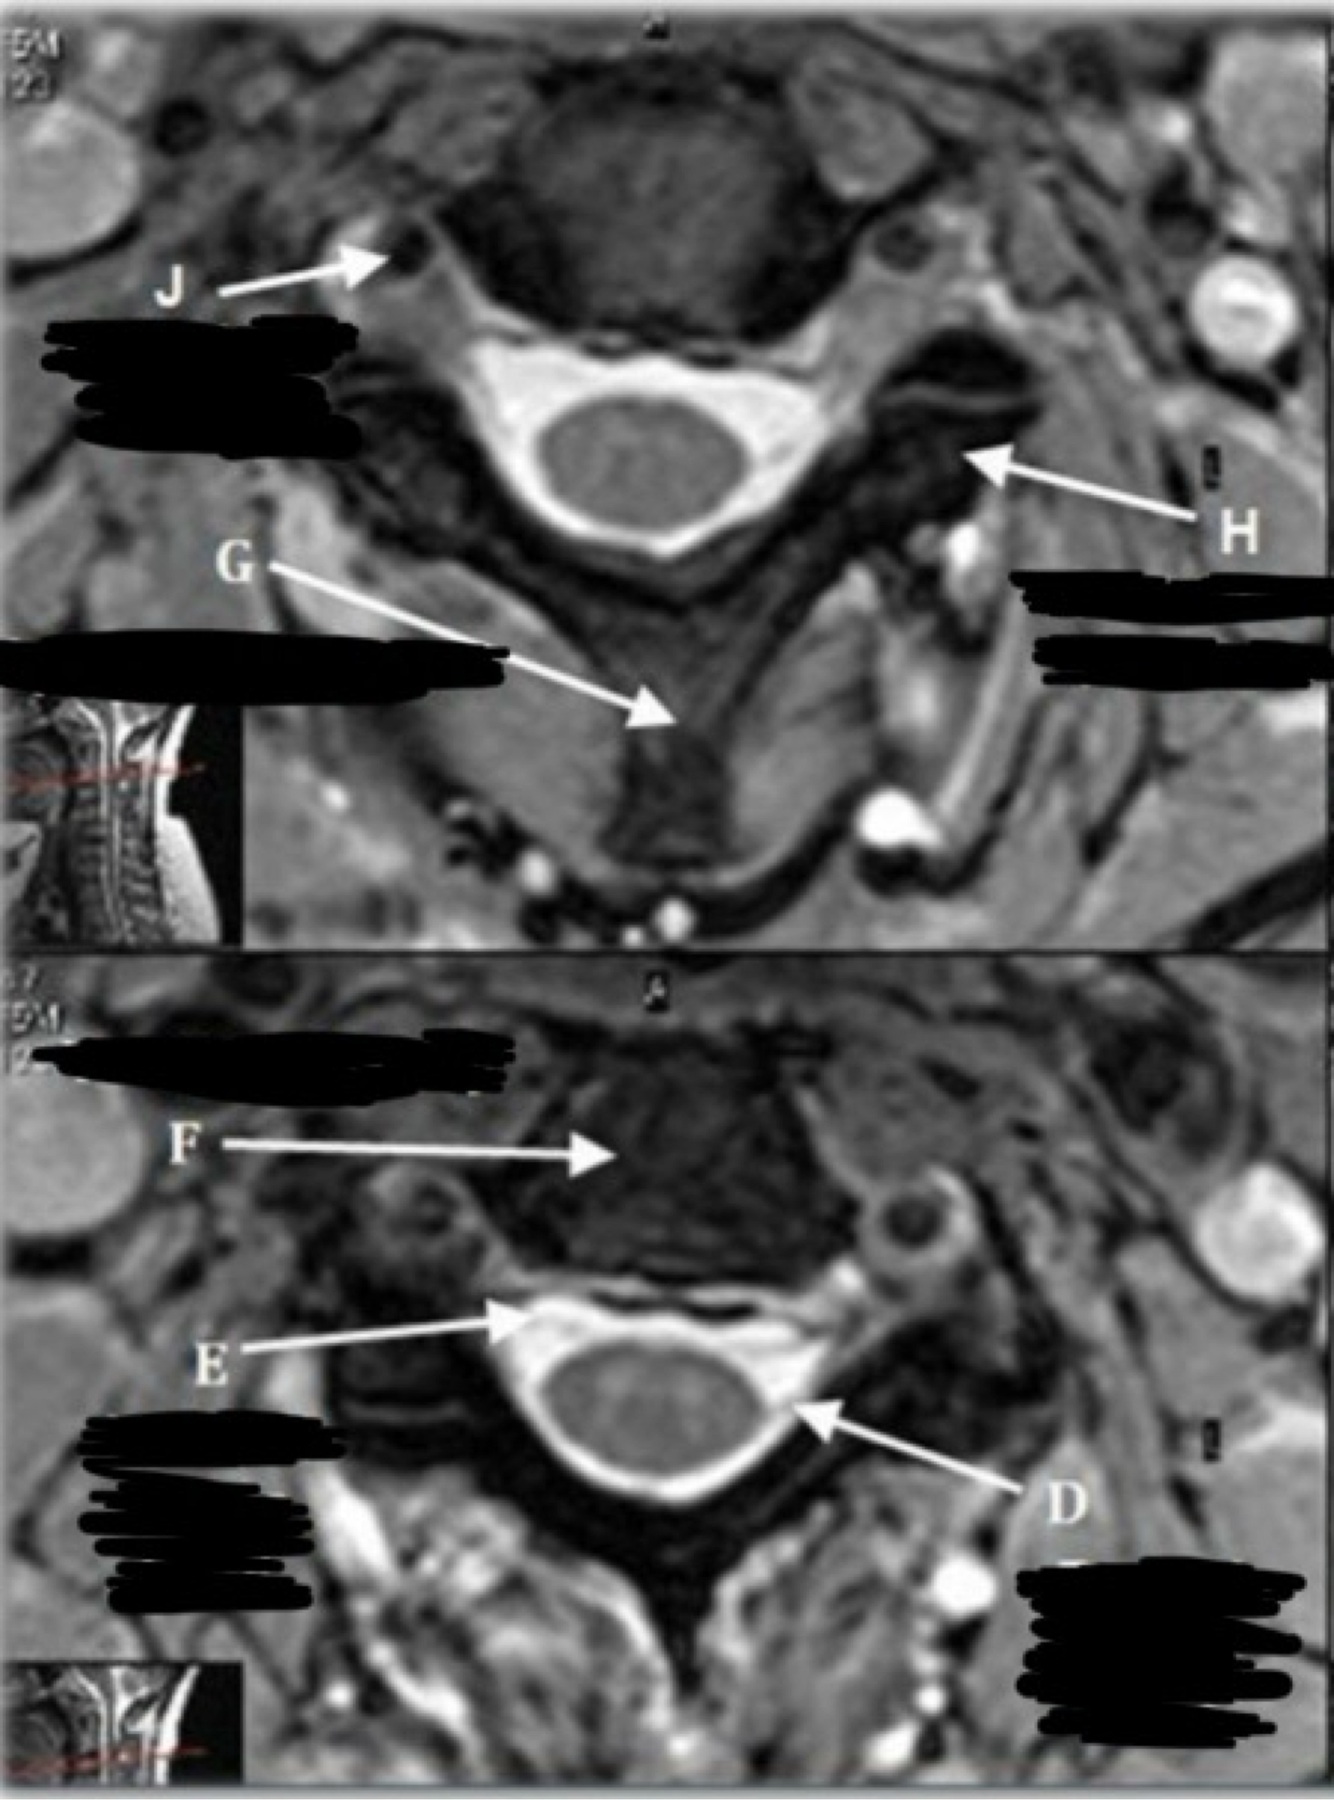

What is letter G?

A

Q

What is letter H?

POSTERIOR LONGITUDINAL LIGAMENT (PLL)

What is letter J?

ANTERIOR LONGITUDINAL LIGAMENT (ALL)